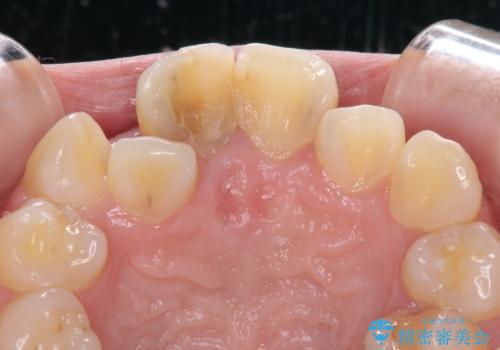

虫歯と抜いたままの奥歯とデコボコの前歯 総合歯科治療

- 放置した虫歯や抜いたままの奥歯、前歯のデコボコを気にして来院された患者様です。

口元の突出感は少なく、下顎の叢生は軽微なものであったので、叢生の強い上顎左右の小臼歯を1本ずつ抜歯し、ワイヤー装置にて矯正治療を行うこととしました。

矯正治療を行う前に、根管治療の必要な上顎前歯と下顎大臼歯の根管治療を行い、矯正治療の途中で下顎の欠損部にインプラント埋入することとし、矯正治療後に補綴治療を行うこととしました。

矯正治療をしたいと思っていたが、放置している虫歯が多いため、どこに相談に行けば良いのか分からずにいたそうですが、当院の総合歯科診療を見て来院されたそうです。